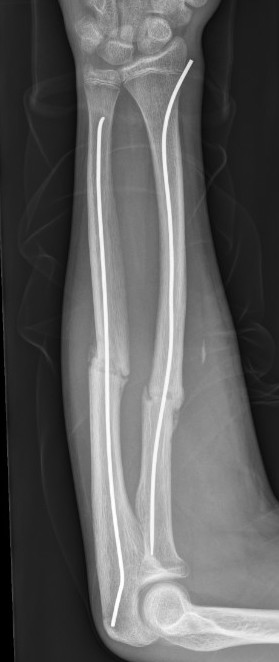

Single v Double Elastic Nail

Dietz et al. J Pediatr Orthop 2010

- retrospective review of 38 children with both bone forearm fractures

- treated only with ulna elastic nail

- all patients had union with restoration of rotation

- two patients had angulation of the radius > 20 degrees that underwent surgical intervention